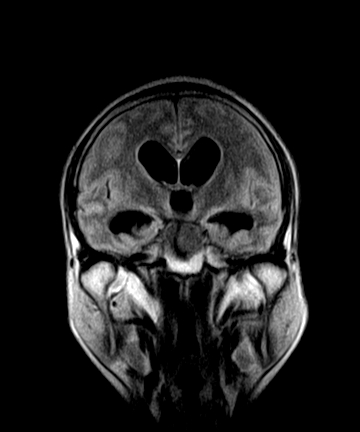

标题: MRI2064:少见病例。男性52,视力下降多年。 [打印本页]

标题: MRI2064:少见病例。男性52,视力下降多年。

四脑室区见混杂信号占位影,脑室系统扩张明显,临近结构显著受压称位,患者52岁,多考虑室管膜瘤可能性大

考虑第四脑室室管膜瘤并梗阻性脑积水;部分性空蝶鞍;左侧上颌窦粘膜下囊肿。